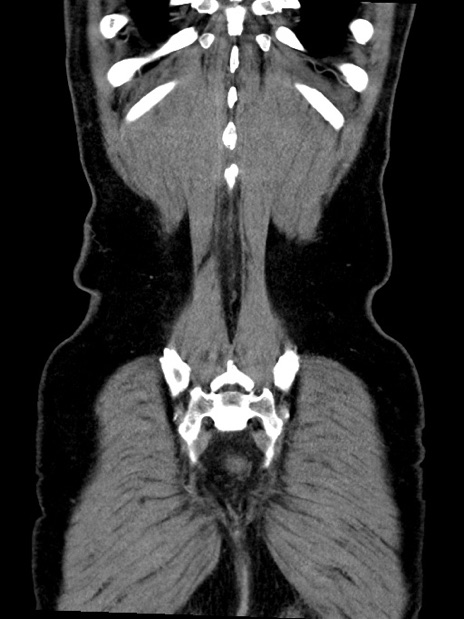

症例35(冠状断像)

【症例】70歳代 男性

【主訴】腹部膨満、嘔吐

【現病歴】昨日より腹部膨満感出現。本日増悪し、仙痛出現。嘔吐あり、受診。

【既往歴】糖尿病、胆摘後

【身体所見】BP 149/80mmHg、HR 74/min、BT 35.9℃、腹部:膨満、軟、圧痛なし。腸雑音減弱あり。上腹部正中切開瘢痕あり。

【データ】WBC 13500、CRP 1.72

横断像